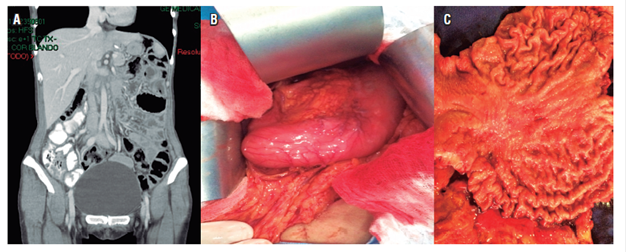

Chemotherapy with capecitabine and cisplatin continued, and May 16 after a decision was made together with the family, a total gastrectomy with D2 lymphadenectomy was performed. Pathology for the product of total gastrectomy showed diffuse type gastric adenocarcinoma with signet ring cells; a 6 x 5 cm lesion; tumor invasion into subserosal fat; lymphovascular and neural invasion; tumor-free proximal and distal edges; 5 of 17 lymph nodes were compromised by tumors staged at pT3pN2; the omentum, left diaphragm, hepatic artery lymph node, and esophageal were tumor free and tested negative for HER2 (Figure 3).

Figure 3 A. Normal abdominal tomography. B. Thickening of the walls near the gastric corpus. C. Surgical piece with corporal gastric lesion.